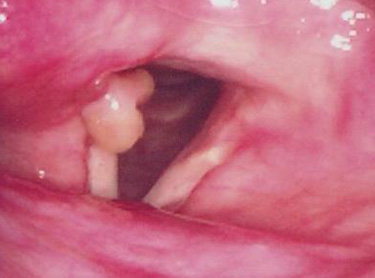

성대육아종